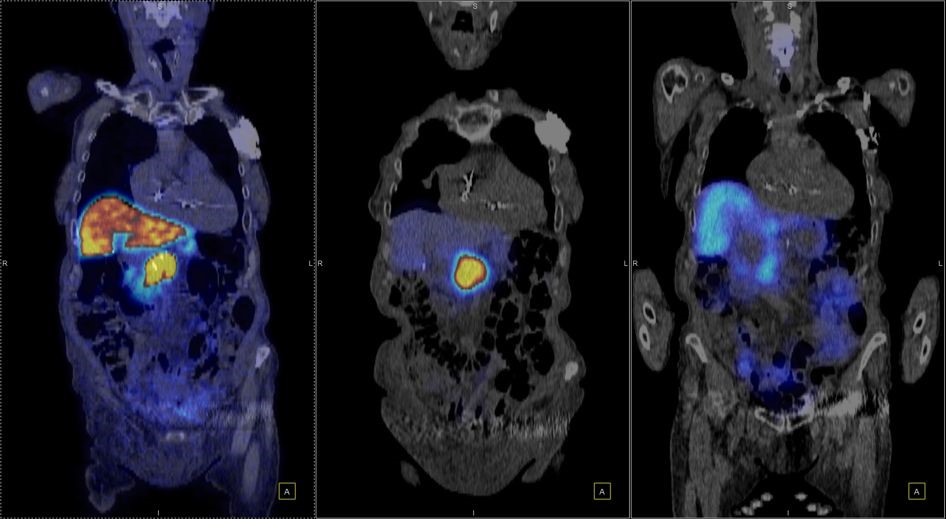

Η Τομογραφία Εκπομπής Ποζιτρονίων (PET) αποτελεί μια εξειδικευμένη μέθοδο της Πυρηνικής Ιατρικής που χρησιμοποιεί μοριακή απεικόνιση για να εντοπίσει και να παρακολουθήσει φυσιολογικές και παθολογικές λειτουργίες του οργανισμού. Συνδυάζοντας τη λειτουργική απεικόνιση της PET με την ανατομική πληροφορία της αξονικής τομογραφίας (CT), η υβριδική εξέταση PET/CT παρέχει εικόνες υψηλής ευκρίνειας και τη δυνατότητα ποσοτικής αξιολόγησης των βιολογικών μηχανισμών σε κυτταρικό επίπεδο.

Η PET/CT αποτελεί εξαιρετικά προηγμένη τεχνική της σύγχρονης ιατρικής απεικόνισης και χρησιμοποιείται τόσο για τη διάγνωση όσο και για την παρακολούθηση της ανταπόκρισης στη θεραπεία.

Οι κυριότερες εφαρμογές της αφορούν την ογκολογία, τη νευρολογία και, σε μικρότερο βαθμό, την καρδιολογία, ενώ συνεχώς αναπτύσσονται νέες χρήσεις σε άλλες ιατρικές ειδικότητες.

Στην ογκολογία, η PET/CT συμβάλλει με εξαιρετική ακρίβεια:

Η εξέταση είναι ανώδυνη και ασφαλής, πραγματοποιείται μετά από ενδοφλέβια χορήγηση ραδιοφαρμάκου (συνήθως ¹⁸F-FDG) και καλύπτει συνήθως ολόκληρο το σώμα – από την κορυφή της κεφαλής έως τα πέλματα.